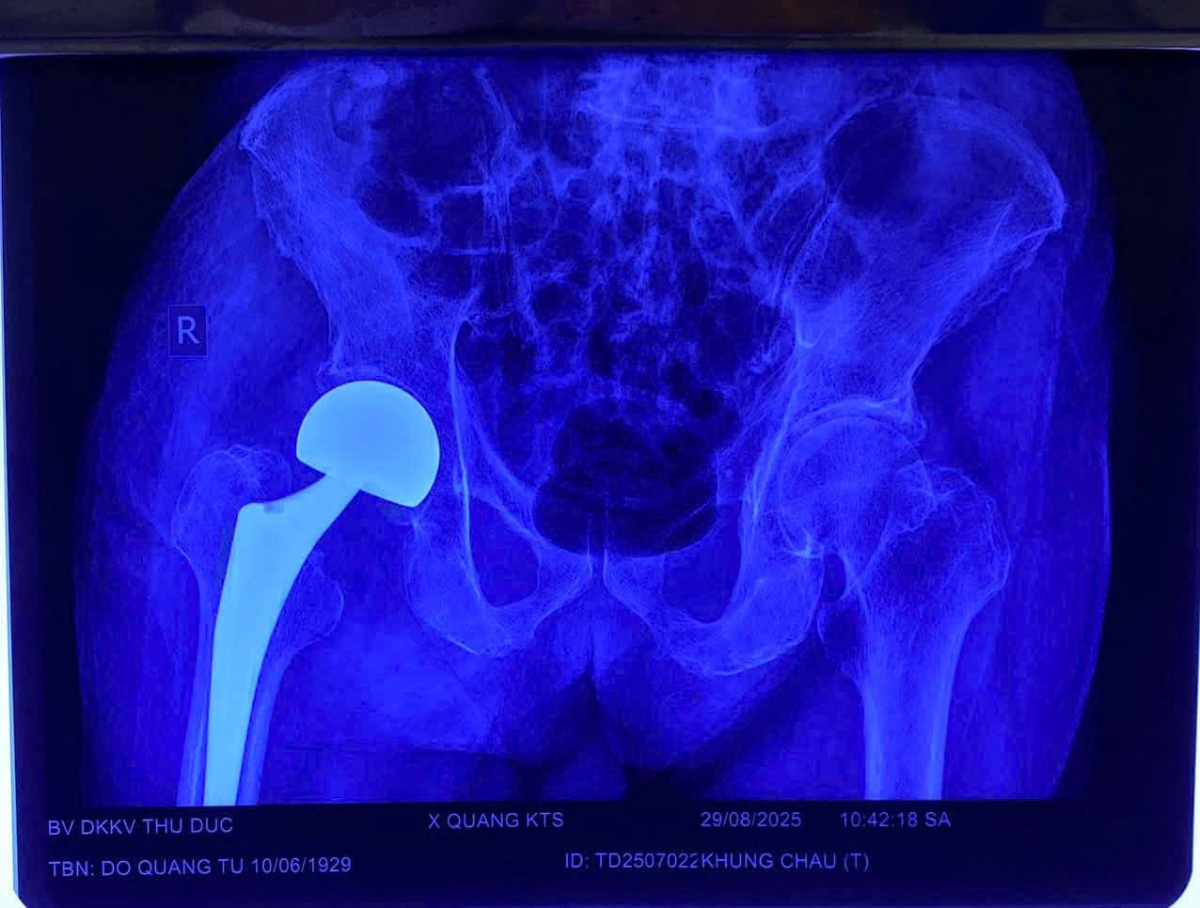

Bệnh viện Đa khoa Khu vực Thủ Đức tiếp nhận cụ ông Đ.Q.T. (96 tuổi, ngụ TP. Hồ Chí Minh) trong tình trạng đau nhiều vùng đùi và háng phải. Người nhà cho biết, cụ bị té ngã khoảng một tháng trước, cơn đau ngày càng tăng khiến việc đi lại và sinh hoạt gặp nhiều khó khăn.

Qua thăm khám và chẩn đoán hình ảnh, bác sĩ xác định cụ bị gãy cổ xương đùi phải. Dù tuổi cao, cụ vẫn minh mẫn, sức khỏe nhìn chung ổn định, có tiền sử bệnh tim mạch và đang sử dụng máy tạo nhịp.

Sau 5 ngày kiểm tra, hội chẩn, ê-kíp do BS.CK2 Đỗ Quang Sang – khoa Chấn thương Chỉnh hình phụ trách đã tiến hành thay khớp háng bán phần. Ca mổ kéo dài 50 phút, diễn ra thuận lợi. Hiện bệnh nhân tỉnh táo, tiếp tục được theo dõi và tập phục hồi chức năng.